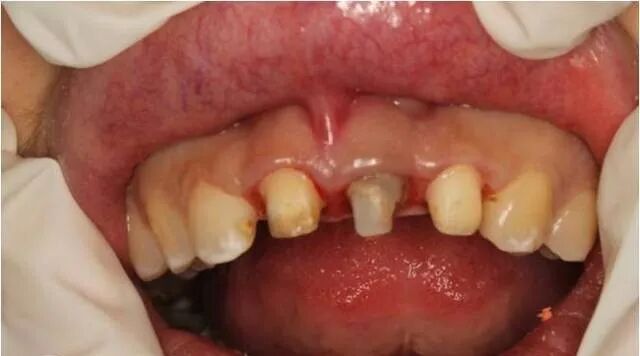

患者自述3年前上前牙因外伤折断在外院做烤瓷牙修复,现烤瓷修复体脱落。

经过检查发现,患者外露牙体组织不够,无法直接进行烤瓷牙重置。建议通过冠延长手术的方法,来使患牙的暴露量增加,然后再通过烤瓷牙进行牙齿的修复及改善牙龈形态的美观。与患者商议,表示接受该修复方案。

术前口内像